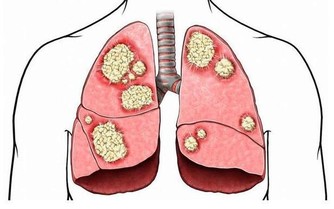

咳嗽是生活中常見的疾病,很多人在患上咳嗽後,喉嚨嚴重不適,

特別是到了夜間睡眠時,咳嗽症狀更加嚴重,因此造成睡眠不佳。

造成咳嗽的原因有許多,感冒引起的喉嚨發炎,

空氣污染,粉塵污染,病毒感染,上火喉嚨發炎等都容易導致咳嗽。